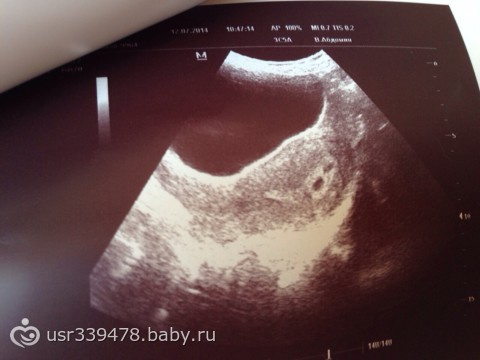

Диагноз выставляется на основе жалоб и данных УЗИ. При помощи этого метода исследования врач может выявить признаки гипертонуса матки.

Утолщенный участок матки давит на плодное яйцо, в итоге оно меняет форму, становится вытянутым. При помощи УЗИ удается увидеть непосредственно и само образование – гематому, оценить ее расположение, размер, поведение и рост. Исходя из этих данных составляется план лечения.

УЗИ позволяет не только определить размер гематомы, но и оценить сердечный ритм эмбриона/плода. С помощью ультразвука удается визуализировать желтое тело, которое вырабатывает прогестерон. При малых размерах желтого тела можно заподозрить абсолютную прогестероновую недостаточность, которая возможно явилась причиной угрозы прерывания беременности.

Основной метод диагностики ретрохориальной гематомы – ультразвуковое сканирование с допплерометрией.

Врач обнаруживает анэхогенные (темные) участки, которые имеют серповидную форму. Специалист определяет размер (объем) гематомы, что важно для прогностической оценки, а также для динамического наблюдения за ее состоянием. Контрольное УЗИ проводят через несколько дней. Если динамика положительная, гематома должна уменьшаться в размерах, становиться более светлой, что свидетельствует о начале процесса организации.